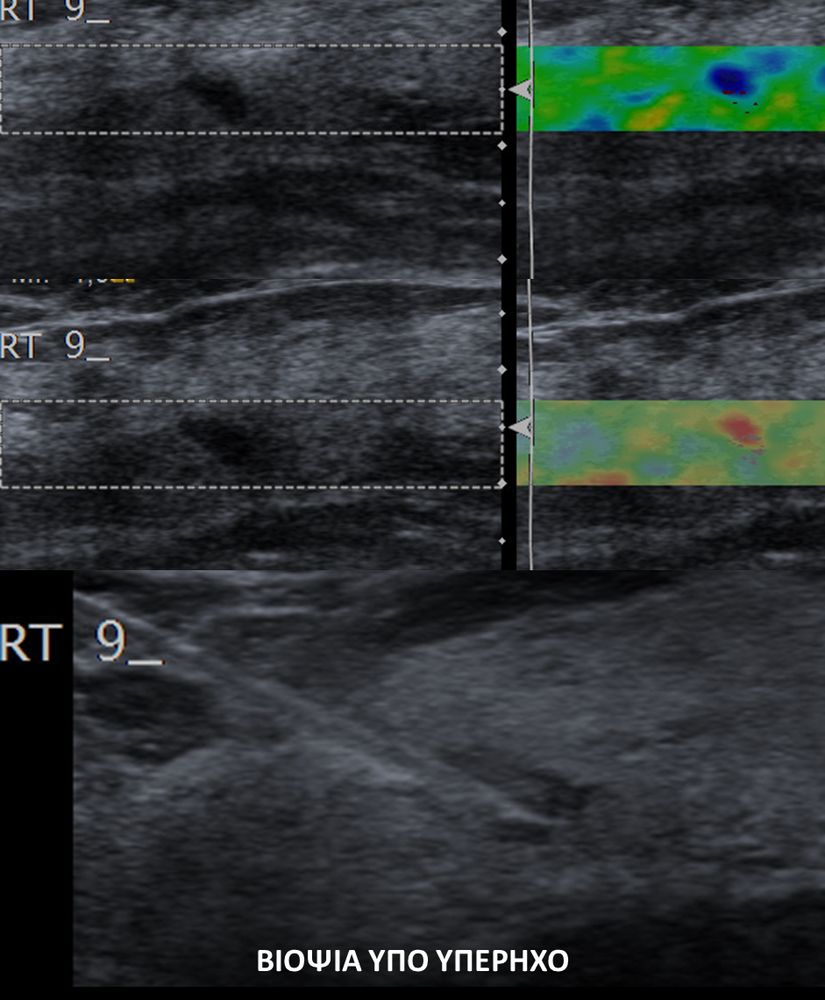

Η ελαστογραφία μαστού είναι μια σύγχρονη υπερηχογραφική μέθοδος που επιτρέπει τη διάκρισητων καλοήθων ογκιδίων από τους κακοήθεις όγκους.

Συνοπτικά ασκείται μια μικρή πίεση στους εντοπισμένους όγκους, μετρώντας την ελαστικότητα τους.

Ο καρκίνος γενικά εμφανίζει μεγαλύτερη σκληρότητα-ελαττωμένη ελαστικότητα σε σχέση με τα καλοήθη ογκίδια και επομένως η ελαστογραφία μπορεί να δώσει τις αναγκαίες πληροφορίες έτσι ώστε να μειώσει τις βιοψίες μαστού μόνο στις απολύτως απαραίτητες.